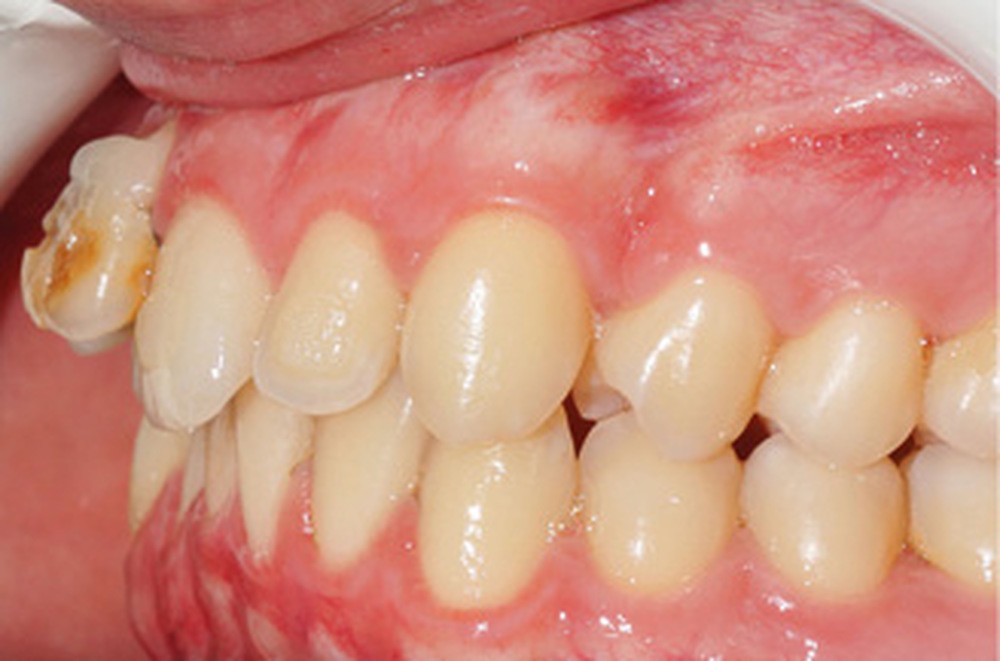

D’un point de vue occlusal, le patient, en denture adulte jeune stable, présente une classe II d’Angle bilatérale de 4 mm, associée à un encombrement maxillaire de 5 mm et mandibulaire de 2 mm. La face mésiale de 21 est centrée avec le plan sagittal médian, la non-concordance des médianes incisives est d’origine mandibulaire (déviation de la médiane mandibulaire vers la gauche) (fig. 1b-d).

Son incisive centrale supérieure droite (11) présente un défaut de structure amélaire sévère, compromettant une technique restaurative pérenne a minima. L’examen de la panoramique (fig. 1e) et de la radiographie rétroalvéolaire de 11 (fig. 1f) objective une fracture coronaire verticale, ainsi qu’une racine grêle et courbe, peut-être en rapport avec un ancien traumatisme [1]. Le rapport couronne clinique/racine clinique est défavorable.